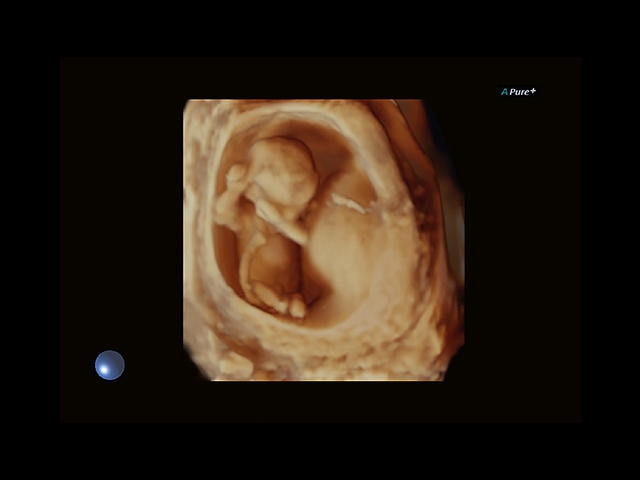

Aplio 500 – ультразвуковой сканер премиум класса, сочетающий в себе быстродействие диагностики и отличное качество визуализации. Более 30 датчиков на выбор, в т.ч. матричные, монокристаллические, 4D, эндоскопические для любых типов исследований. Ультразвуковой сканер позволяет изучать анатомические структуры в высоком разрешении.

Обновленная версия легендарного УЗ-сканера. Стационарный аппарат экспертного класса Aplio 500 Toshiba NEW, визуализирует анатомические структуры в высоком разрешении. Модель позволяет выявить микрокальцификаты, новообразования, нарушения в работе сердца, сосудов и мышц. Присутствует функция виртуальной эндоскопии, 4D-сканирования, эластометрии тканей, УЗИ с контрастированием. За повышение качества изображения отвечают технологии ApliPure и Superb Microvascular Imaging. Первая задействует возможности пространственного и частотного кодирования, формирует цельный визуальный ряд с сохранением клинических маркеров. Вторая улучшает отображение микрососудистого русла, используя доплеровский эффект. Модель оснащена 21-дюймовым монитором, имеет 4 активных порта. Возможно подключение педиатрических, интраоперационных, лапароскопических и чреспищеводных датчиков.

4D:

Да